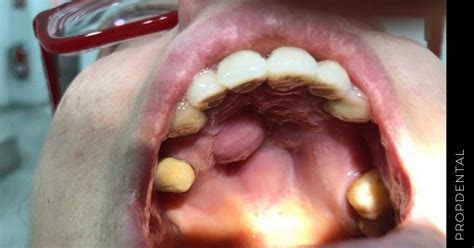

- Torus Palatinus: El torus palatinus es una protuberancia ósea benigna que se desarrolla en el centro del paladar duro. Suele tener una causa genética, es asintomático y no duele.